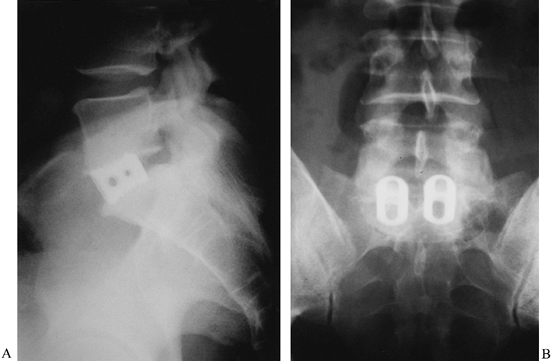

Figure 146.3. Anteroposterior (A) and lateral (B)

radiographs of a 39-year-old man with persistent low-back pain. He had

a history of remote sciatica, which resolved but has now developed into

persistent low-back pain despite maximal physical therapy. These

radiographs show classic changes of degenerative disc disease: a

narrowed disc space, sclerotic endplates, and marginal osteophyte

formation. The L4–5 disc was normal on MRI, and thus no discography was

indicated. -